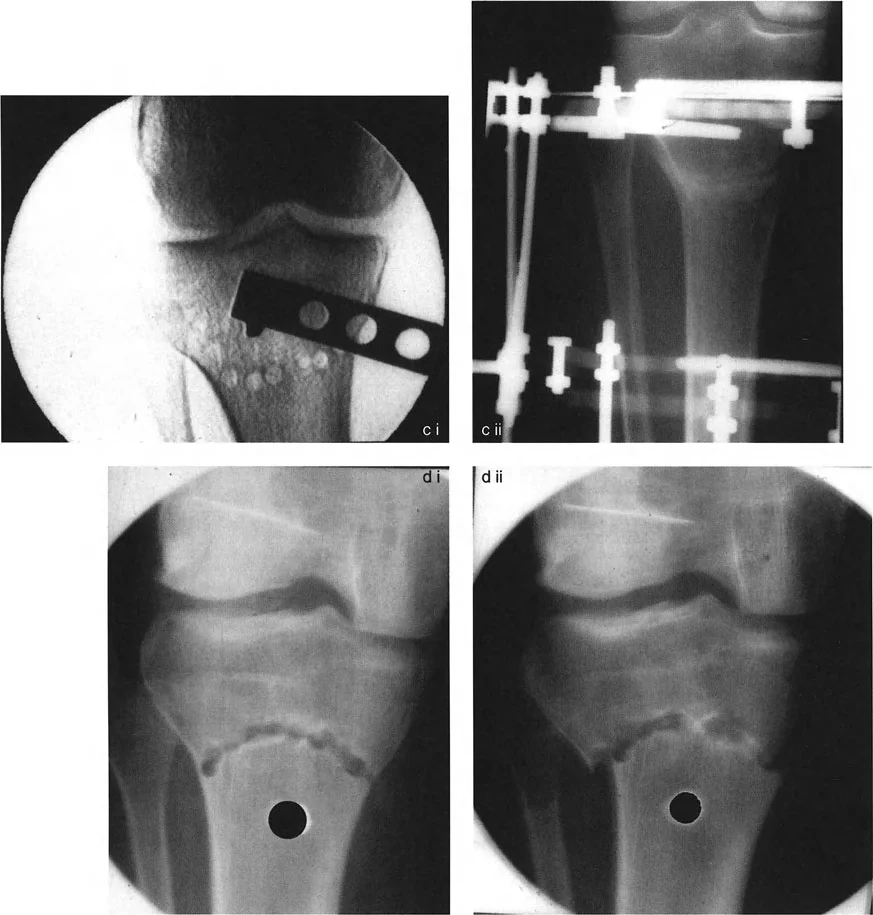

التصوير بالأشعة السينية (X-rays):

- أشعة الساق الكاملة الواقفة (Full-length Standing X-rays): هذه هي الأداة التشخيصية الأكثر أهمية لتشوهات الأطراف. يتم أخذ الصورة بينما يقف المريض، مما يسمح بتقييم المحور الميكانيكي للطرف بأكمله (من الورك إلى الكاحل) تحت تأثير تحمل الوزن. تتيح هذه الصور للجراح قياس زوايا محددة بدقة وتحديد "مركز دوران التشوه" (CORA) – وهو النقطة المحورية التي يجب أن يتم التصحيح حولها.

- أشعة مقاطع محددة: قد تكون هناك حاجة لأشعة سينية لمفاصل معينة (مثل الركبة أو الكاحل) من زوايا مختلفة لتقييم حالة المفصل والغضاريف.

ما هو قطع العظم التقويمي (Osteotomy)

قطع العظم التقويمي هو إجراء جراحي يتم فيه قطع العظم وإعادة محاذاته لتصحيح التشوه. بعد قطع العظم، يتم تثبيته في الوضع الجديد باستخدام ألواح ومسامير، أو مسامير نخاعية، أو مثبتات خارجية، للسماح له بالالتئام في المحاذاة الصحيحة. يُعد هذا الإجراء حجر الزاوية في علاج تشوهات الأطراف.

تقنيات قطع العظم المختلفة

هناك عدة طرق لقطع العظم، يختار الجراح الأنسب منها بناءً على نوع التشوه وشدته وموقعه:

- قطع العظم بالوتد المفتوح (Opening Wedge Osteotomy): يتم عمل قطع في العظم، ثم يتم فتح فجوة صغيرة في جانب واحد من العظم لتقويم التشوه. غالبًا ما تتطلب هذه الفجوة ترقيعًا عظميًا لملئها.

- قطع العظم بالوتد المغلق (Closing Wedge Osteotomy): يتم إزالة قطعة عظمية على شكل وتد من العظم لإغلاق التشوه. هذه التقنية تؤدي إلى تقصير طفيف في طول الطرف.

- قطع العظم القبة (Dome Osteotomy): وهي التقنية التي سنركز عليها لتميزها ودقتها.

قطع العظم القبة المتقدم (Dome Osteotomy)

أهمية التخطيط الدقيق لقطع العظم

إن نجاح جراحة تصحيح تشوهات الأطراف يعتمد بشكل كبير على التخطيط المسبق الدقيق. هذا التخطيط أشبه برسم خارطة طريق هندسية تضمن أن كل خطوة جراحية تقود إلى النتيجة المرجوة. يعتمد هذا التخطيط على "مبادئ بالي" التي تحدد ثلاثة متغيرات هندسية أساسية في كل حالة:

- مركز دوران التشوه (CORA - Center of Rotation of Angulation): هذه هي النقطة المحورية للتشوه في العظم. يحددها الجراح من خلال رسم محاور الطرف قبل الجراحة.

- محور تصحيح الزاوية (ACA - Angulation Correction Axis): هذه هي النقطة التي يدور حولها الجزء البعيد من العظم لتصحيح التشوه. يتحكم الجراح في هذه النقطة عن طريق وضع المفصلات على المثبت الخارجي أو نقطة الارتكاز للوحة التثبيت.

- مستوى قطع العظم (Osteotomy Level): هذا هو الموقع الفعلي الذي يتم فيه قطع العظم. يتحكم الجراح بشكل كامل في هذا المتغير، ويتم اختياره بناءً على عوامل مثل الأنسجة الرخوة، وجودة العظم، ونوع الأجهزة المستخدمة.

النتيجة النهائية للتصحيح تعتمد كليًا على كيفية ارتباط هذه المتغيرات الثلاثة ببعضها البعض. الفشل في التخطيط الدقيق يمكن أن يؤدي إلى "تشوهات ثانوية" غير مرغوب فيها، مثل انحراف المحور الميكانيكي أو ترجمة (إزاحة) العظم.